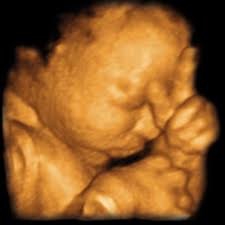

Baby impressions is an elective 3d 4d ultrasound imaging facility. Fetal measurements (by request) hear & see baby's heartbeat. 3d & 5d ultrasound images and 4d ultrasound video can be obtained at any stage. Baby's estimated weight and position. 30 weeks is best for 3d/4d images of what your baby will look like after it is born. Water can improve the quality of an ultrasound. At this stage, the baby has put on some weight and filled out to make features more visible, yet still enough fluid in front of baby's face to obtain great images. You'll notice that what you see varies a lot by the number of weeks of gestation. It was a very special day for my husband and i. In addition to 3d 4d ultrasound, baby bloom is known for our spectacular hd live ultrasound imaging. We do not perform medical ultrasounds. When i was 31 weeks i went back for our first 3d/4d ultrasound and it was even more special being able to see my son's face for the very first time. Book now *free rescan if face can't be seen at all.

Check out our before and after photo album on facebook and our website photo gallery for examples! Water can improve the quality of an ultrasound. Sounds like you have a very active baby! Fetal measurements (by request) hear & see baby's heartbeat. This cutting edge imaging is also known as 5d ultrasound. @cricketandhorse, i have one done at the office each week (not a 3/4d though). If you are having multiples this is also a good time to capture 3d pictures of the babies. The baby has had time to build up body fat, but still has room to move around. All digital pictures and video from your session delivered to phone or email. We are now booking in our brand new studio in downtown shawnee. Gender confirmation (by request) 5 black & white pictures. In addition to 3d 4d ultrasound, baby bloom is known for our spectacular hd live ultrasound imaging. I think they look sooo squished in there, i haven't seen any really good 3d/4d pictures past 35 weeks.

In these final weeks before your baby's birth, several subtle changes are taking place that will prepare. 4d or 4 dimensional scans build on the technology of 3d scans. Video recording of your session on babyflix. Each week in pregnancy can look slightly different. 3d/4d & hd ultrasound 8 week baby in 2d, 3d/4d & hd ultrasound pictures 12 week baby in 3d 4d baby ultrasound pictures 15 week baby in 2d, 3d/4d & hd ultrasound pictures 23 week baby in 3d 4d & hdlive baby pictures 13.5 weeks 14 weeks 15 weeks 15.2 weeks twins 16 weeks 18 weeks 22 weeks 24 weeks 27 weeks 29 weeks 30 weeks 31 weeks with.